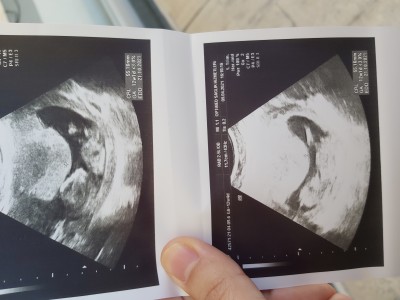

Nub teorisi bilenler lutfenn

Nub teorisi anlayanlar lutfenn

erkek gibi sanki cnm

Rabbim gönlüne göre versin erkek hissettim sen ne istiyosun

Hayırlı sağlıklı imanlı bir evlat olsn ben görünce erkek dedm

Benim ultrasonumla çok benziyor doktor bana erkek dedi hayırlı eli ayağı düzgün evlatlar olsunlarda gerisi mühim değil Rabbim gonlindekini versin canim

Evet canım erkek

Erkek doğdu şuan 7 aylık